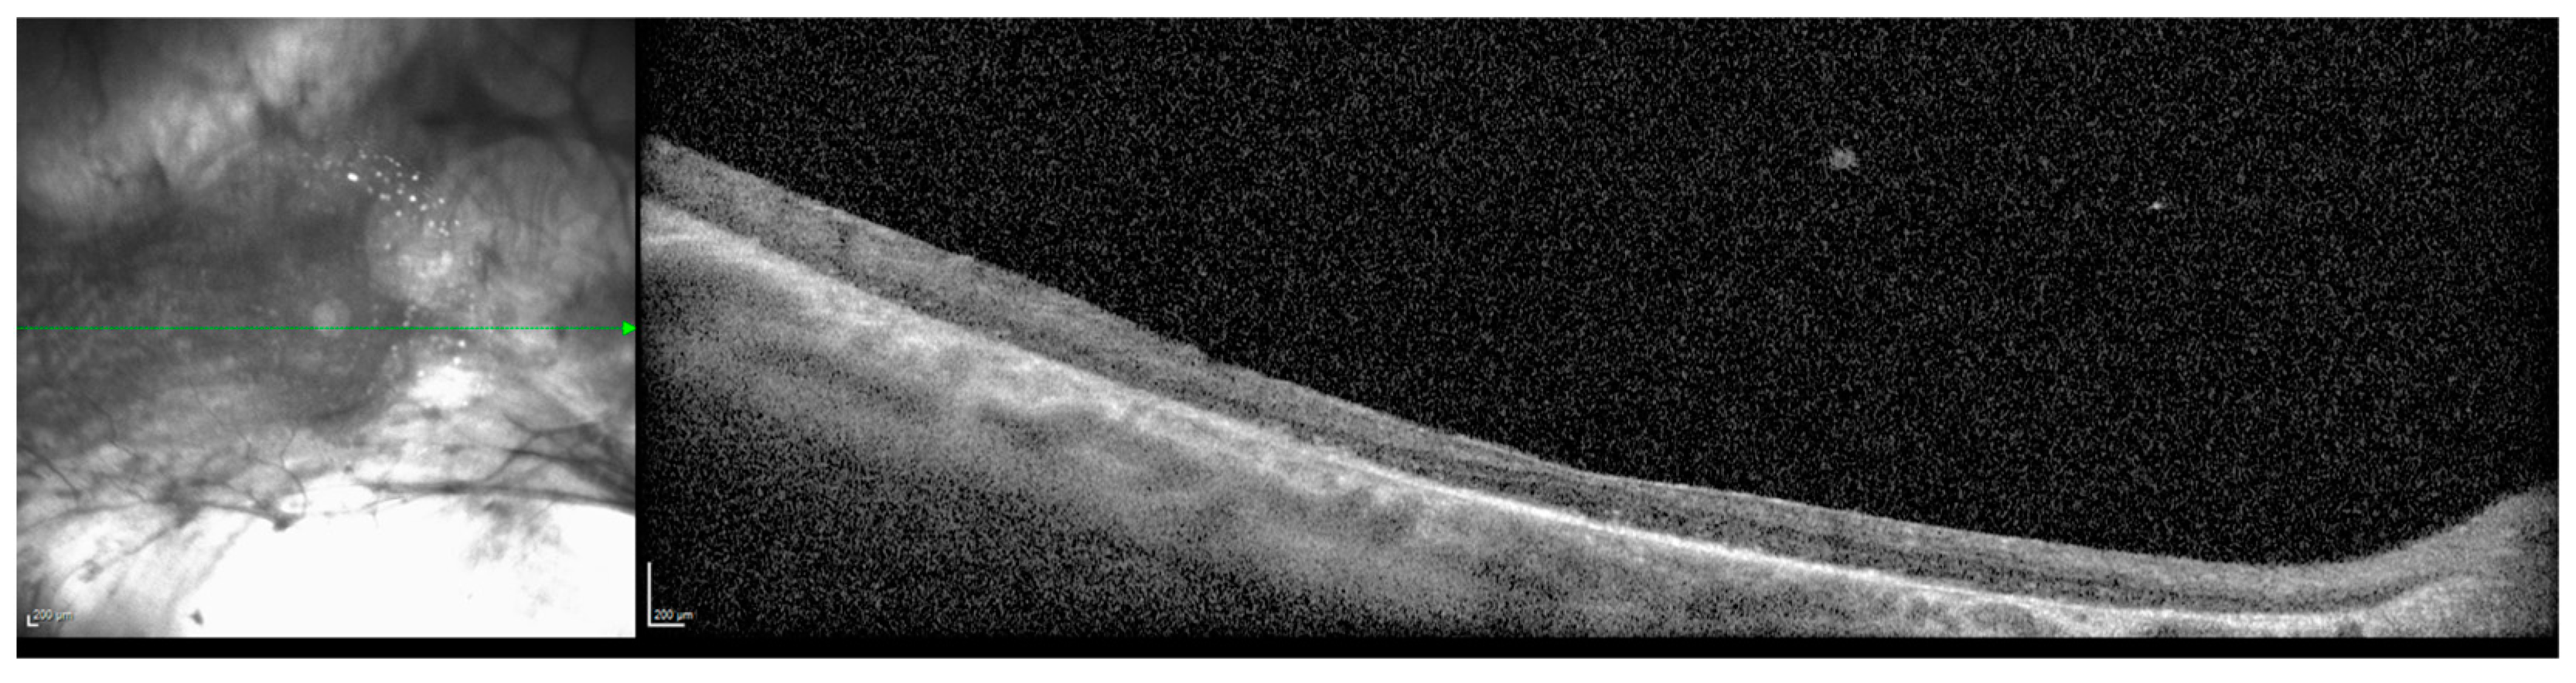

Figure 3.

Vitreous hemorrhage (arrow), right eye, age 32.

The patient continued to attend surveillance appointments for the next decade with a relatively stable clinical course. Next generation sequencing and Sanger sequencing of the KIF11 gene and flanking introns performed in consultation with a medical geneticist revealed a previously undocumented, heterozygous de novo c.210+2del intronic variant of the KIF11 gene (Prevention Genetics, 2017, Marshfield, WI, USA, NM_004523.3). The patient’s biological parents and two siblings declined clinical examination and genetic testing for the variant. At age 32, a small right vitreous hemorrhage was identified, and there was concern for progression and temporal foveal encroachment of the patient’s chronic RD (Figure 3). The patient underwent a right scleral buckle procedure with external drainage, limited pars plana vitrectomy, cryoretinopexy, and intravitreal injection of SF6 gas. Following postoperative recovery, visual acuity in the right eye improved to 20/200 from a baseline of 20/400, and the macula and fovea remained attached (Figure 4).